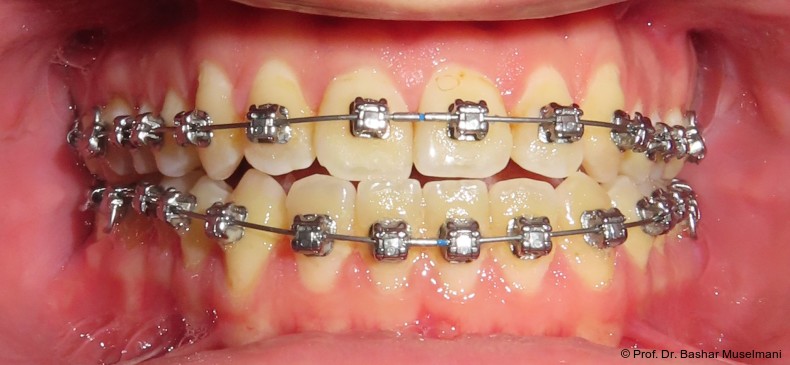

Die Abbildungen 1 bis 3 zeigen die initiale klinische und radiologische Ausgangssituation.

Apparative Versorgung

Die Behandlung erfolgte mittels einer festsitzenden Multibracketapparatur unter Verwendung passiver selbstligierender Brackets (Damon Ultima System) im Ober- und Unterkiefer.

Zur sagittalen Korrektur wurden intermaxilläre Klasse III-Gummizüge eingesetzt.

Zu Beginn der Nivellierungsphase wurden in beiden Kiefern 0.013" CuNiTi-Bögen eingesetzt (Abb. 4a–e).